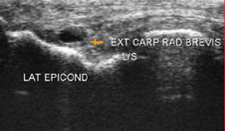

Tennis elbow involves inflammation and degeneration of the Extensor Carpi Radialis Brevis (ECRB) tendon where it inserts into the elbow (lateral epicondyle). This muscle is a pure wrist extensor and so the demand placed upon it during forceful and repeated wrist extension is high. Add to that, age (weakening the tendons and the muscles) and then activity (bricklaying, typing) and it is not surprising that the tendons of this muscle can tear.

DIAGNOSING TENNIS ELBOW

Tennis Elbow requires a thorough physical examination by an experienced hand therapist, once the diagnosis is complete, a treatment plan is prepared to get you back to the things you love. Action Rehab Hand Therapy Clinic hand therapists will ask, where the pain is, what sort of pain is it (shooting? burning?). Action Rehab Hand Therapy Clinic hand therapists will assess your strength, your motion and your occupations to see what the symptoms and most importantly what the cause may be. In most cases, your medical history and physical exam will be enough for us to make a diagnosis. However, if an MRI, ultrasound or X-Ray is required our Physiotherapists, and Occupational Therapists can read and interpret the results.